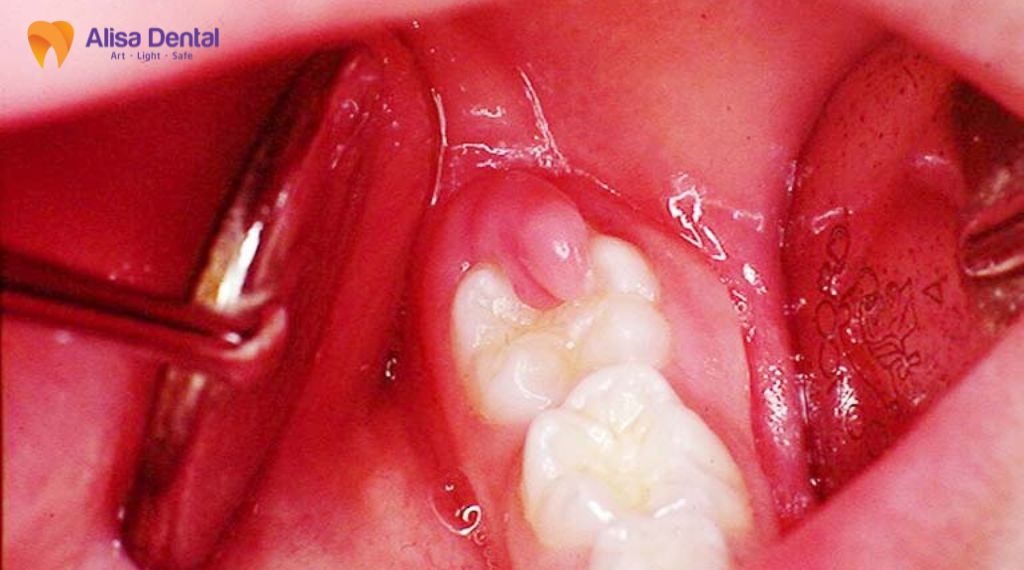

Trường hợp 2: Răng bị chấn thương (gãy, vỡ, nứt)

Những tai nạn sinh hoạt, va đập mạnh hoặc thói quen cắn đồ cứng (khui bia, nhai đá lạnh) có thể khiến răng bị tổn thương cấu trúc nghiêm trọng.

- Gãy, vỡ lộ tủy: Khi một mảng răng lớn bị vỡ ra làm lộ chấm đỏ hoặc hồng (điểm tủy) ra ngoài môi trường miệng, vi khuẩn sẽ ngay lập tức tấn công gây viêm nhiễm cấp tính.

- Nứt ngầm (Cracked Tooth Syndrome): Đây là trường hợp nguy hiểm và khó phát hiện hơn. Vết nứt có thể rất nhỏ, mắt thường khó thấy nhưng đủ sâu để cắt đứt mạch máu nuôi dưỡng tủy hoặc tạo đường dẫn cho vi khuẩn len lỏi vào trong. Lâu ngày, tủy răng sẽ bị chết dần mòn mà bệnh nhân không hay biết cho đến khi nướu sưng lên hoặc chụp X-quang thấy nang chân răng.